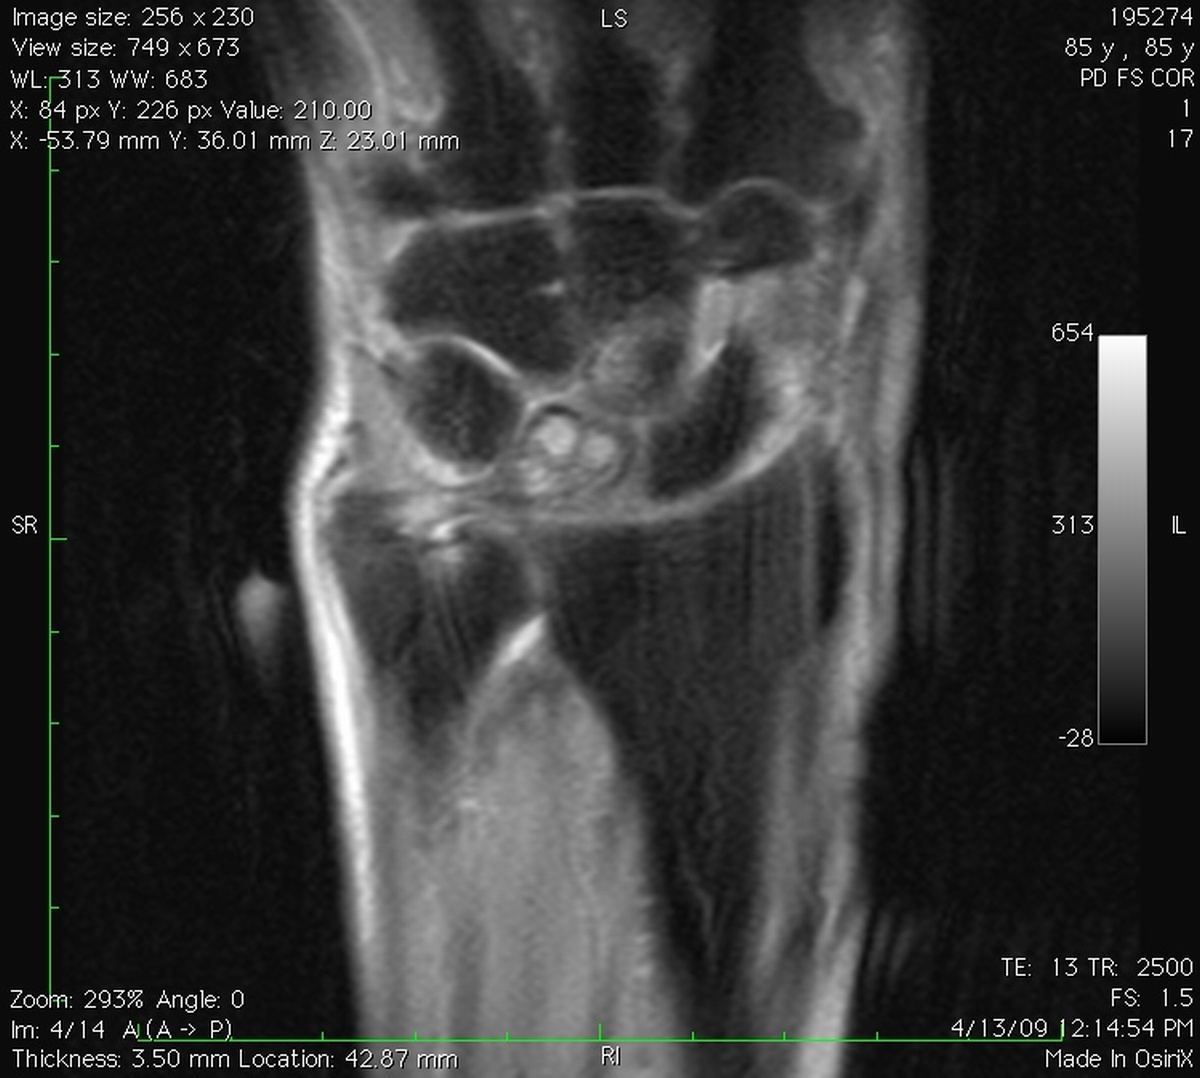

Clinical Example: Lunate Cyst

This imaging series was obtained for evaluation of a one month history of painful pronosupination in an active 85 year old man whose daily exercises include pushups.

lunate cyst